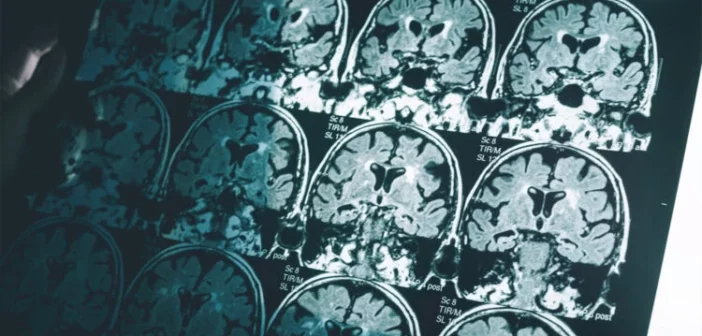

Структура и связи в мозге могут играть ключевую роль в том, насколько успешно люди среднего и пожилого возраста управляют своими финансами.

Новое исследование, опубликованное в Archives of Gerontology and Geriatrics, показало, что люди с более здоровыми тканями мозга и лучшей связностью между определенными областями лучше справляются с повседневными финансовыми задачами. Эти результаты важны, поскольку снижение когнитивных функций может сделать пожилых людей уязвимыми для мошенников.

• МРТ-сканирование для анализа структуры мозга и связности между его областями,

Исследователи обнаружили, что более высокие финансовые способности связаны с увеличенным объемом тканей в областях мозга, отвечающих за язык и извлечение информации из памяти. Особенно значимой оказалась связь между левым нижним лобным регионом, помогающим вспоминать языковые конструкции, и успешным управлением финансами.

Другим важным фактором оказалась связность между левым нижним теменным регионом и лобной корой. Эти связи помогают автоматически извлекать арифметические факты из памяти. В то же время люди с низким уровнем финансовых способностей чаще полагались на области, отвечающие за активные вычисления, что может усложнять обработку информации в реальной жизни.